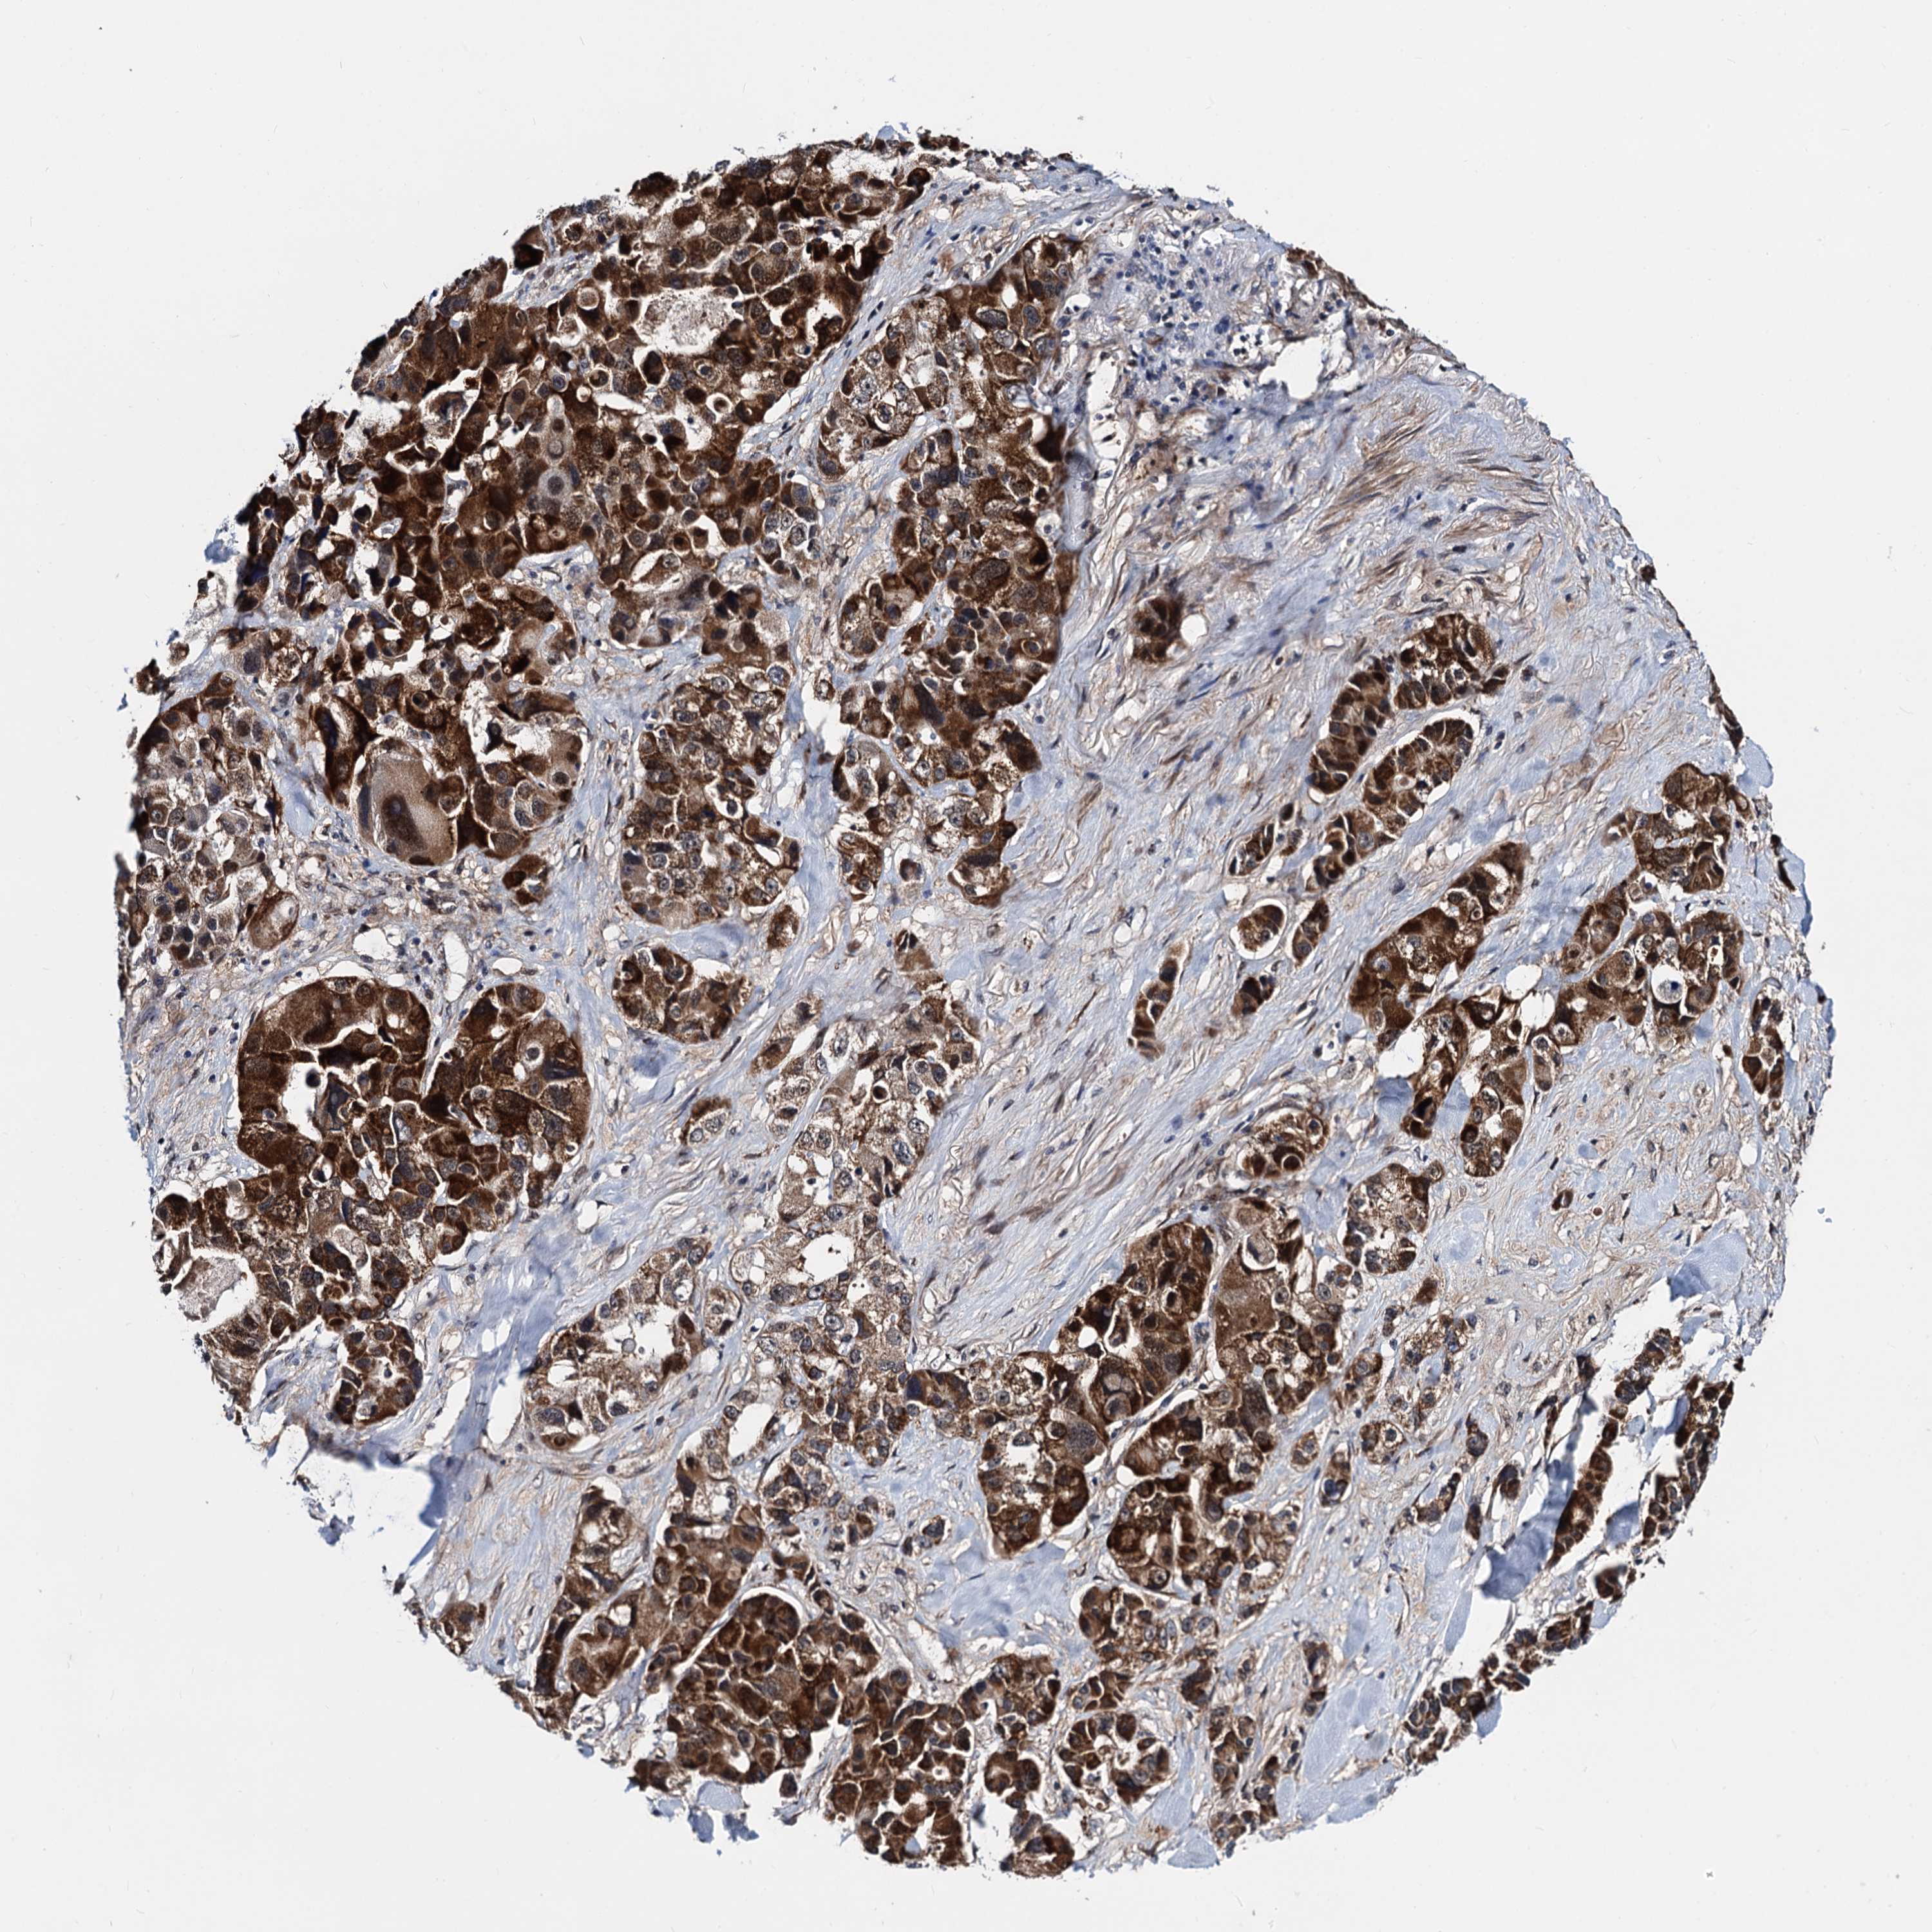

CANCER LUNG CANCER Show tissue menu

LUAD TCGA LUAD VALIDATION LUSC TCGA LUSC VALIDATION PROTEIN LUAD CPTAC PROTEIN LUSC CPTAC PROTEIN EXPRESSION